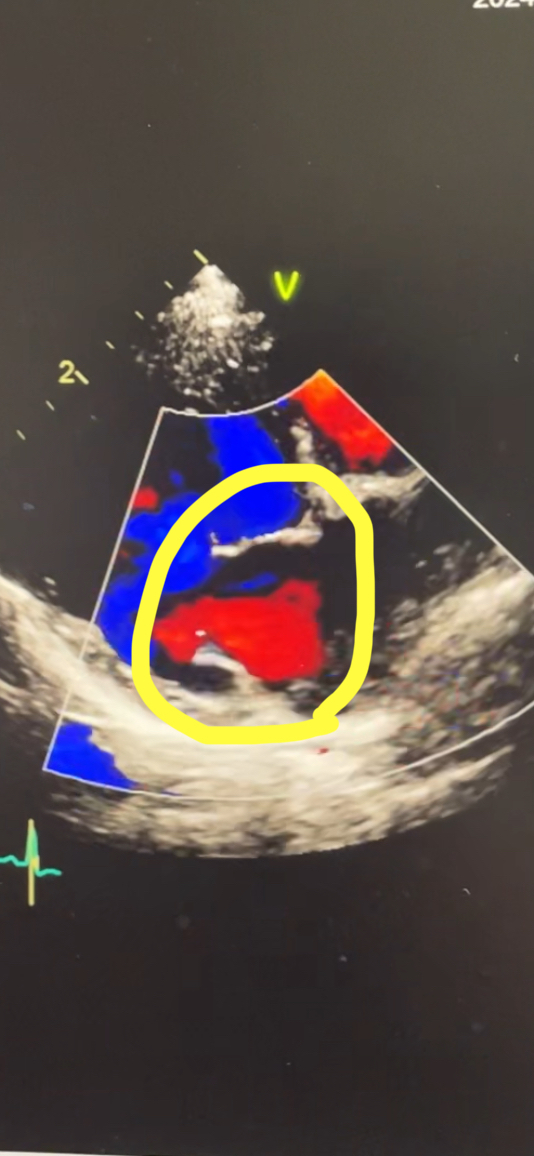

エコー画像ビフォーアフター

チーくんの心臓病(僧帽弁閉鎖不全症)エコー画像、術前と術後の比較です

まずは術前ですが、黄色で囲んだ閉まるはずの弁が大きく開いているのが分かります。